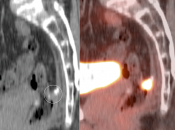

- Fusion of Images

- Beam Hardening

- Diaphragmatic Mismatch

- Linear Hand Motion

- Attenuation Correction